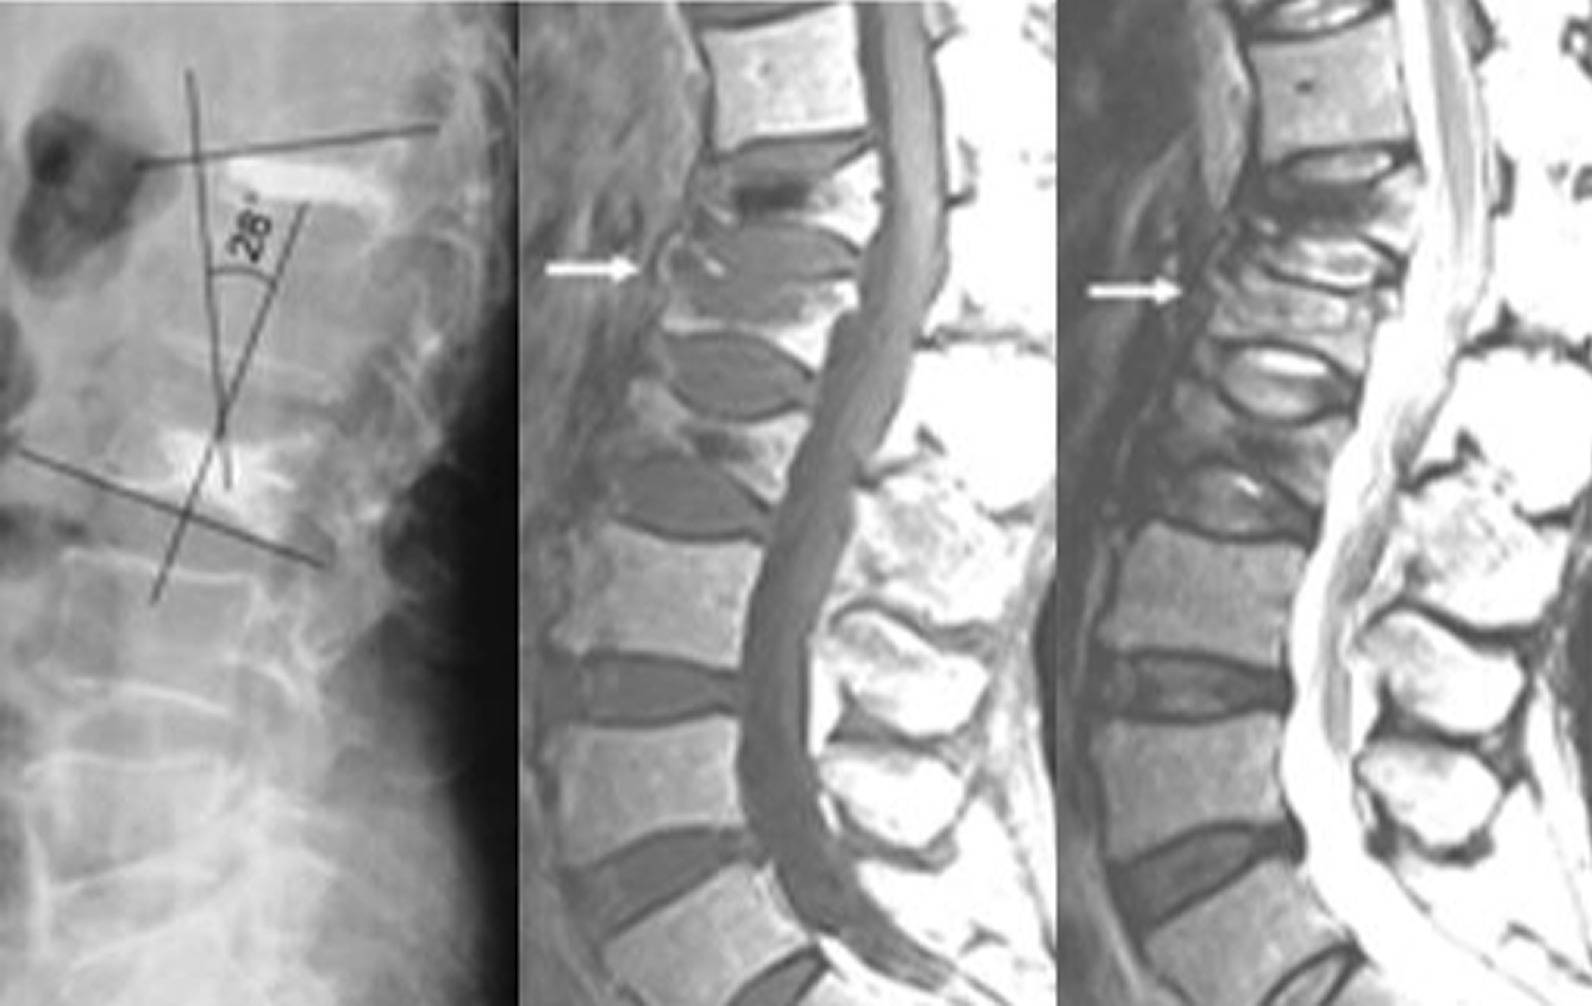

Fig. 1.

Cobb angle after PVP surgery

In this study, the patients were divided into two groups, namely A and B, based on the treatment that they underwent. Patients in group A underwent PVP, which included 30 patients. Patients in group B underwent PKP, which included 31 patients. The follow-up period was 1 year. Statistical analysis was performed using SPSS 26.0. The general characteristics of the patients in the two included age, gender, height, and weight. Age, height, and weight were compared using two independent sample t-tests, with P > 0.05, whereas gender was compared using a Chi-square test with P > 0.05. No statistically significant difference was found in the general characteristics of the two groups of patients (Table 1). Two independent sample t-tests were performed to compare surgical time, fluoroscopy frequency, VAS score, bone cement volume, and Cobb angle between the two groups of patients. The comparison of surgical time, fluoroscopy frequency, and VAS score between the two groups showed no statistically significant difference (P > 0.05). Conversely, the comparison of the amount of bone cement and Cobb angle between the two groups (Figs. 1, 2) showed a statistically significant difference (P < 0.05), with Group A being greater than Group B (Table 2). The leakage rate of bone cement intervertebral space in Group A was 20% (6/30), which was higher than that in Group B (3.23%, 1/31). Following up for one year, the incidence rate of vertebral fractures in Group A (36.67%, 11/30) was significantly higher than that in Group B (12.90%, 4/31). The leakage rate of bone cement intervertebral space and the incidence rate of vertebral fractures in the two groups were compared using the chi-square test (Significance at P < 0.05). The comparison between the two groups was statistically significant. The leakage rate of bone cement intervertebral space and the incidence rate of vertebral fractures in group A were both higher than those in group B (Table 2).

In this study, patients were divided into Groups A and B. Patients in Group A were treated with PVP, whereas those in Group B were treated with PKP to explore the risk of PVP and PKP for osteoporotic vertebral compression fractures on the occurrence of interbody fractures. The general characteristics of patients in the two groups, including age, gender, height, and weight, were statistically analyzed and the results showed no statistically significant difference in the general characteristics of the two groups (P > 0.05). The surgical time, fluoroscopy frequency, and postoperative VAS score of the two groups showed no statistically significant difference (P > 0.05). Conversely, the amount of bone cement, Cobb angle, the leakage rate of the intervertebral space, and the fracture rate of the sandwich vertebral body showed statistically significant differences between the two groups (P < 0.05).

The diffusion area of bone cement in the vertebral body observed during PVP was larger than that observed during PKP; owing to the higher amount of bone cement in PVP, bone cement can be easily distributed to the upper and lower endplates of the vertebral body during PVP. Studies have confirmed that the strength and hardness of bone cement distributed in the upper and lower endplates are greater than those of undistributed bone cement in the vertebral body [19, 20]. Therefore, the strength and hardness of the vertebral body during PVP are greater, and the mechanical conductivity of the sandwich vertebral body is greater, making it more prone to fractures. Theoretically, bone cement might increase the pressure on the adjacent disk, resulting in the deformation of the adjacent endplate, causing fractures in the endplate and nearby cancellous bone. Thus, stress and strain changes can further exacerbate, ultimately leading to adjacent vertebral fractures [21]. In the present study, when the Cobb angle was large, the fracture rate of the dissected vertebral body was higher, and PVP was higher than PKP. When spinal kyphosis occurs, local biomechanics change, and a body’s center of gravity shifts forward, requiring greater back muscle strength to maintain spinal balance. When the interlayered vertebral body cannot withstand the increased stress, fractures occur. In the present study, the leakage rates of bone cement in the intervertebral space of the two groups were 20% and 3.23%, respectively. The leakage of intervertebral space may be through the endplate and hollow fissure of the fracture. When the bone cement leaks into the intervertebral space, the force of the intervertebral space is transmitted to the sandwich vertebral body during the spinal load movement, subjecting the sandwich vertebral body to “double” force, making it prone to fractures. Herein, after the one-year follow-up, the fracture rates of the sandwich vertebral body in the two groups were 36.67% and 12.90%, respectively. Rates in the PVP group were significantly higher than those in the PKP group. Wang M et al. have confirmed that intervertebral disc leakage of bone cement is a risk factor for subsequent vertebral fractures [22].